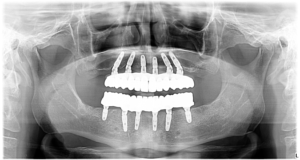

În cazul Domnului A. a fost nevoie de o reabilitare totală cu ajutorul a 12 implanturi dentare, inserate astfel: 6 la maxilar și 6 la mandibulă.

În radiografia prezentată mai jos puteţi observa situaţia dentară iniţială a pacientului nostru, dar şi rezultatul obţinut după inserarea implanturilor convenţionale.

Pacientul a optat pentru o lucrare finală realizată din zirconiu, fixată pe implanturile standard. Zirconiul este un material extrem de rezistent, care are în același timp un aspect natural!